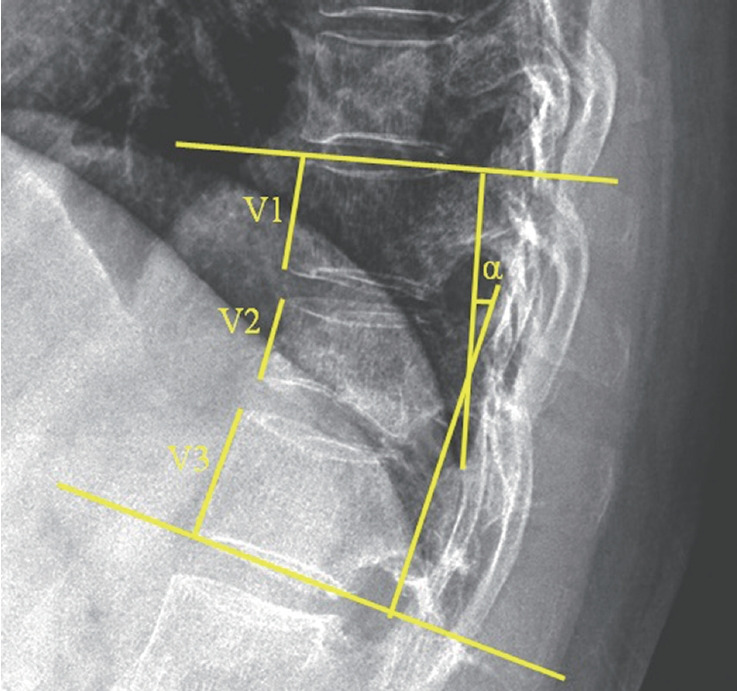

Methods: A retrospective analysis included 86 thoracic/lumbar compression fracture patients from 2014 to 2022 at a medical center. Forty-two patients received romosozumab (monthly injections for 1 year) followed by 1 year of denosumab, while 44 underwent vertebroplasty followed by denosumab injections biannually for 2 years. Outcomes were assessed using the Numerical Rating Scale (NRS) for pain, bone mineral density (BMD), vertebral compression ratio, and Cobb angle over 12 months.

Results: At 12 months, the romosozumab group showed a greater reduction in NRS scores (4.90 ± 1.01 vs. 4.27 ± 1.34, p = 0.015) and a higher increase in lumbar BMD (0.8 ± 0.5 vs. 0.5 ± 0.3, p = 0.000) compared to the vertebroplasty group. There were no significant differences in changes in hip total BMD and femur neck BMD (p = 0.190, p = 0.167, respectively). Radiographic assessments showed no significant differences in vertebral compression ratio (14.7% vs. 14.8%; p = 0.960) or Cobb angle (4.2° vs. 4.9°; p = 0.302). The incidence of major osteoporotic fractures was lower in the romosozumab group (7.1% vs. 25.0%, p = 0.051), with similar rates of cardiovascular events in both groups (4.8% vs. 9.1%, p = 0.716).